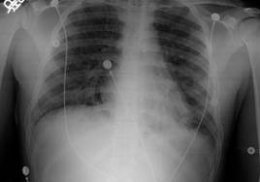

Туберкулез

Туберкулез является инфекционным заболеванием, которые вызывается микобактериями, характеризуется развитием клеточной аллергии, гранулем, возникающих в различных органах либо тканях, полиморфной картиной. Особенно характерно поражение лимфатической системы, суставов, костей, кожи, нервной системы, глаз, мочеполовых органов, легких. При отсутствии должного лечения туберкулез начинает прогрессировать, заканчивается фатально.

Болезнь очень заразна, передается воздушно-капельным путем. Необходимо тщательная изоляция в лечебном учреждении во время болезни. Особенно часто начинается при ослабленном иммунитете, при неправильном либо несвоевременном лечении легко перерастает в сложную, трудно излечимую форму. Симптомы: кашель, кровохарканье, повышенная температура, похудение, бледность. Читать далее